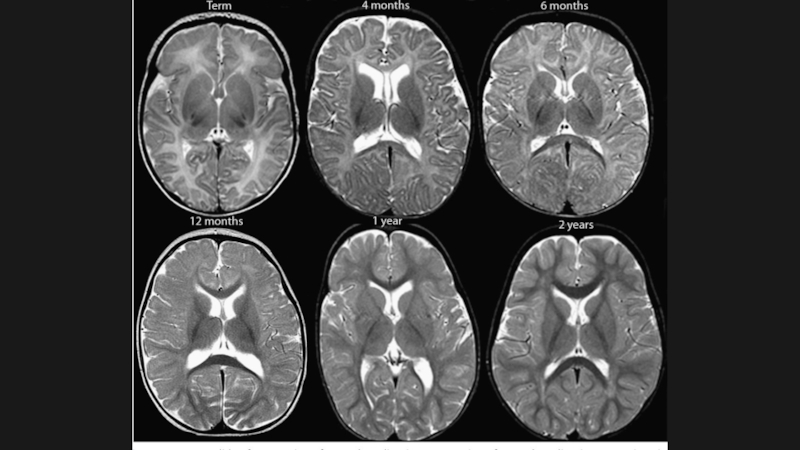

Слайд 10

4 мес

Слайд 116 мес.

6 мес.

Слайд 1212 мес.

12 мес.

Слайд 1318 мес.

18 мес.

Слайд 142 года

2 года